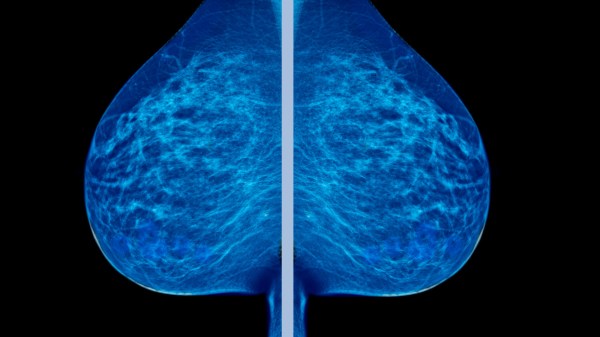

They conducted a randomized controlled trial of 89,835 Canadian women ages 40-59 and followed up on them 25 years later. Half of the women got regular mammograms and the other half had no mammograms whatsoever during that period. Here are the results:

** Mammograms No Mammograms

Number of women 44,925 44,910

Number of breast cancer deaths 500 (1.113%) 505 (1.124%)**

As you can see, the difference is negligible.

Furthermore, 1 in 424 women who received mammograms were misdiagnosed (false positives) and given unnecessary treatment including radiation, surgery, and chemotherapy.

Reviving this thread because I saw this today and thought it was interesting. The side effects from overtreatment for breast cancer kill as many (and probably slightly more) people than are saved who actually have breast cancer who would’ve died had it not been for the mammogram and treatment.

There is a chart on the side showing the NNT are 1000, so you have to screen 1000 women to save 1 life.

It is a wash, and when you factor in all the illness and psychological trauma from overdiagnosis it is possibly much worse to get screened than not.